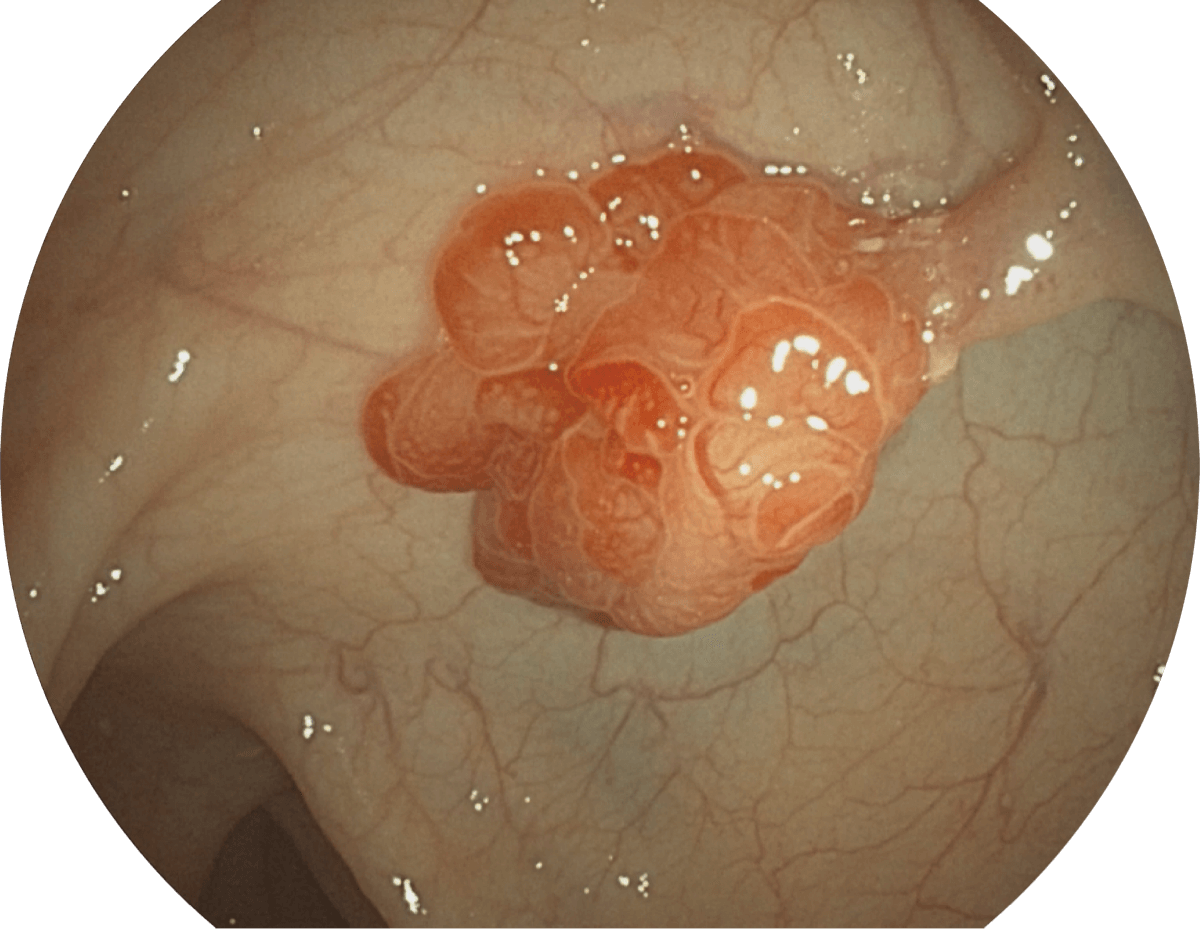

具有聚谱成像技术(SFI)及光电复合染色成像技术(VIST),可完美呈现粘膜细节及病变特征。

(Spectral Focused lmaging, SFI)